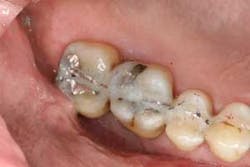

Figures 5a and 5b: Osseous surgery in the upper right quadrant with debridement of root surfaces and then regeneration.

Briefly, during osseous surgery, the upper right molars were treated with a combination of autograft and platelet-derived growth factor/Beta-tricalcium phosphate along with a porcine collagen graft (figures 5a and 5b). The upper left osseous surgery consisted of the same treatment (figures 6a and 6b), but also included the extraction of a hopeless tooth No. 15. Once again, the anterior osseous surgery consisted of the same regenerative materials as the former surgeries but with the addition of a porcine soft-tissue graft (figures 7a, 7b, and 7c). After the initial healing phase, the patient was placed on a strict home-care regimen and was seen every eight to 12 weeks for hygiene recare. The patient maintained excellent hygiene throughout the five-year follow-up period.